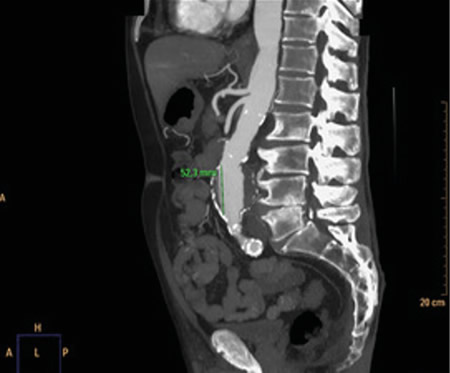

No es solo dolor lumbar: manifestación atípica del aneurisma de aorta

Not just low back pain: atypical manifestation of aortic aneurysm

La rotura de aneurisma de aorta supone el síntoma principal en hasta un 25 % de los casos de la patología de aneurisma de aorta, que constituye una entidad potencialmente mortal. También puede aparecer con menor prevalencia como lumbalgia, coxalgia e, incluso, gonalgia, no comentándolo como dolor vertebral o neuropático, sino como irritación a nivel de psoas ilíaco como primera sintomatología.

Se estima que solo en un 50 % de los casos aparece la triada clásica del aneurisma, por lo que es necesario tener un alto nivel de alerta para sospecharlo, ya que la hipovolemia puede estar contenida por un hematoma peritoneal.

Figura 1

Figura 2